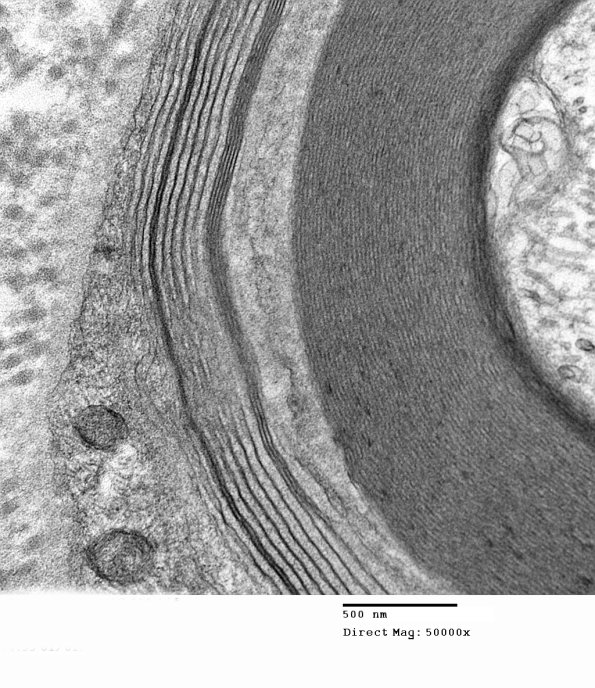

This axon shows wide spaced myelin at several magnifications. The hemi-desmosomes are often seen at nodes but are not typical parts of WSM. (electron micrographs)